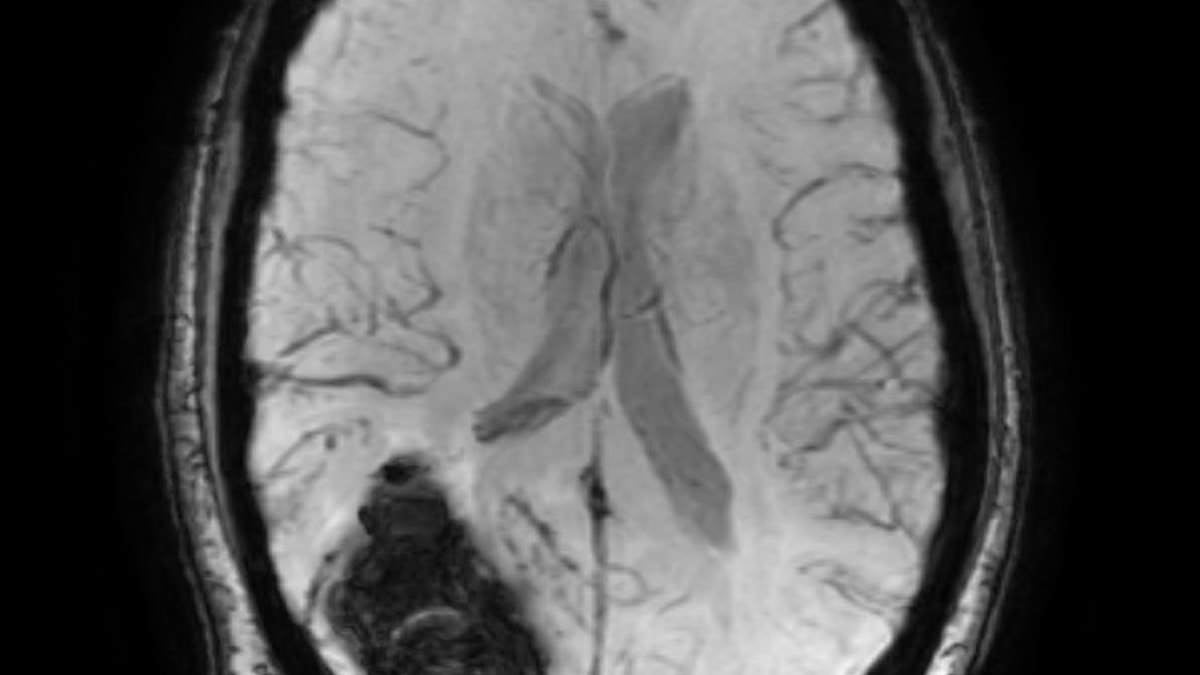

Dr. Tim Williams, a 69-year-old Florida physician who previously directed Delray Medical Center's Proton Therapy Institute, survived a fall that caused a brain bleed and a nine-day coma, underwent a bedside craniotomy, and endured a lengthy recovery before returning home. Nine months on, he’s about 80% back to normal, has shifted toward radiation oncology research, and credits Delray Medical Center’s staff and stroke expertise with saving his life. He emphasizes that anyone experiencing stroke symptoms should seek care at a stroke center to maximize chances of survival.